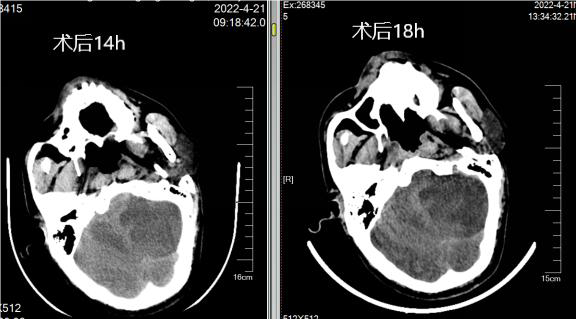

术后即刻、14小时与18小时复查头颅CT

病历夹什么径技·第152期|串联营病历夹:川陕大营_https://www.jmylbn.com_新闻资讯_第29张

术后14小时小脑梗死灶水肿,四脑室显影不佳,是否需要急诊后颅去骨瓣减压?

认为去骨瓣更好,但该患者进行去骨瓣选择时家属选择不去骨瓣,结果发现患者预后不佳。